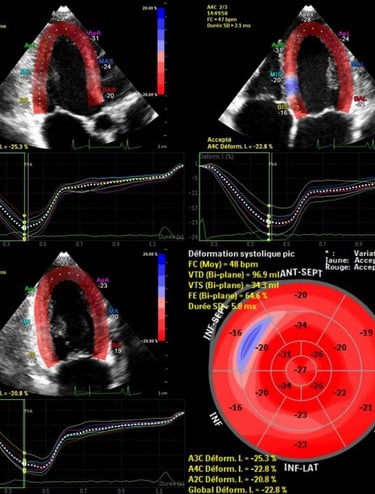

Échographie cardiaque

Évaluation de la structure, des valves et de la fonction du cœur en temps réel.